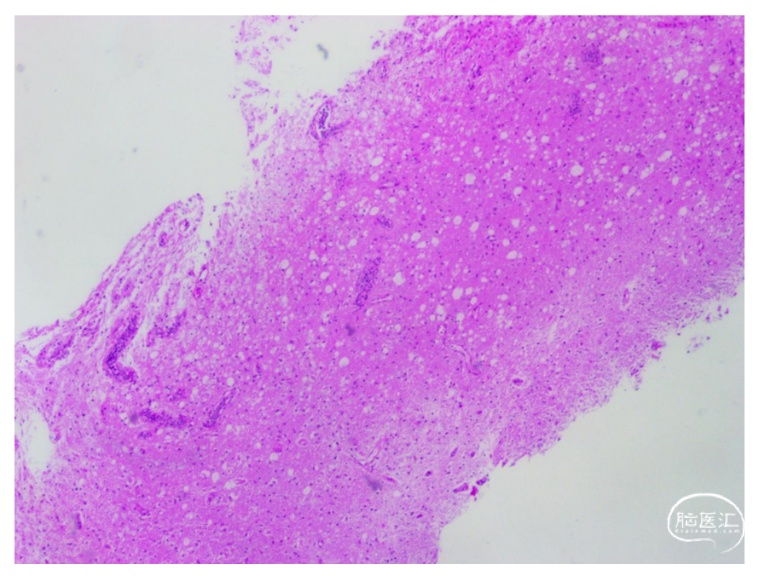

术后常规病理提示:血管内见单个散在或小巢团样聚集的单核异型细胞,免疫组化结果:CD20 +,CD79a +,PAX-5 +,CD3 个别+,CD5 个别+;CD68 +,CD163 +,GFAP 散在+,Olig-2 散在+,NF 部分保留,MBP -,IDH1(H09) -,ATRX 存在,P53 -,Ki-67 5%,SV40 -。特殊染色结果:变色酸2R 部分-,髓鞘(坚牢蓝) 部分髓鞘染色-,PAS -,PASM -,结合现有免疫组化结果,考虑血管内B细胞淋巴瘤(图2)。

IVLBCL的病理诊断具有高度特异性,其核心特征为肿瘤细胞选择性局限于血管腔内,尤其是小动脉、毛细血管及静脉内,形成“血管内栓塞”样结构,而血管外间质及脑实质内通常无肿瘤细胞浸润(图4)。本例患者的立体定向活检组织学检查显示,血管内见单个散在或小巢团样聚集的单核异型细胞。肿瘤细胞核染色质粗糙,核仁明显,核分裂象易见,符合大B细胞淋巴瘤的形态学特征。此外,IVLBCL免疫组化特征:肿瘤细胞强表达CD20及CD79a,证实其B细胞起源,CD20的弥漫性强阳性是IVLBCL的关键诊断标志,也是利妥昔单抗(抗CD20单抗)治疗的靶点。近年研究提示,IVLBCL常伴MYD88 L265P突变及BCL2重排,与弥漫大B细胞淋巴瘤(DLBCL)的分子特征部分重叠,但其血管内生长模式可能与肿瘤细胞黏附分子(如CD54/ICAM-1)异常表达相关。本例未行二代测序,未来可结合分子分型探索个体化治疗靶点[3,4]。本例患者术后病理及免疫组化结果符合IVLBCL的病理特征。